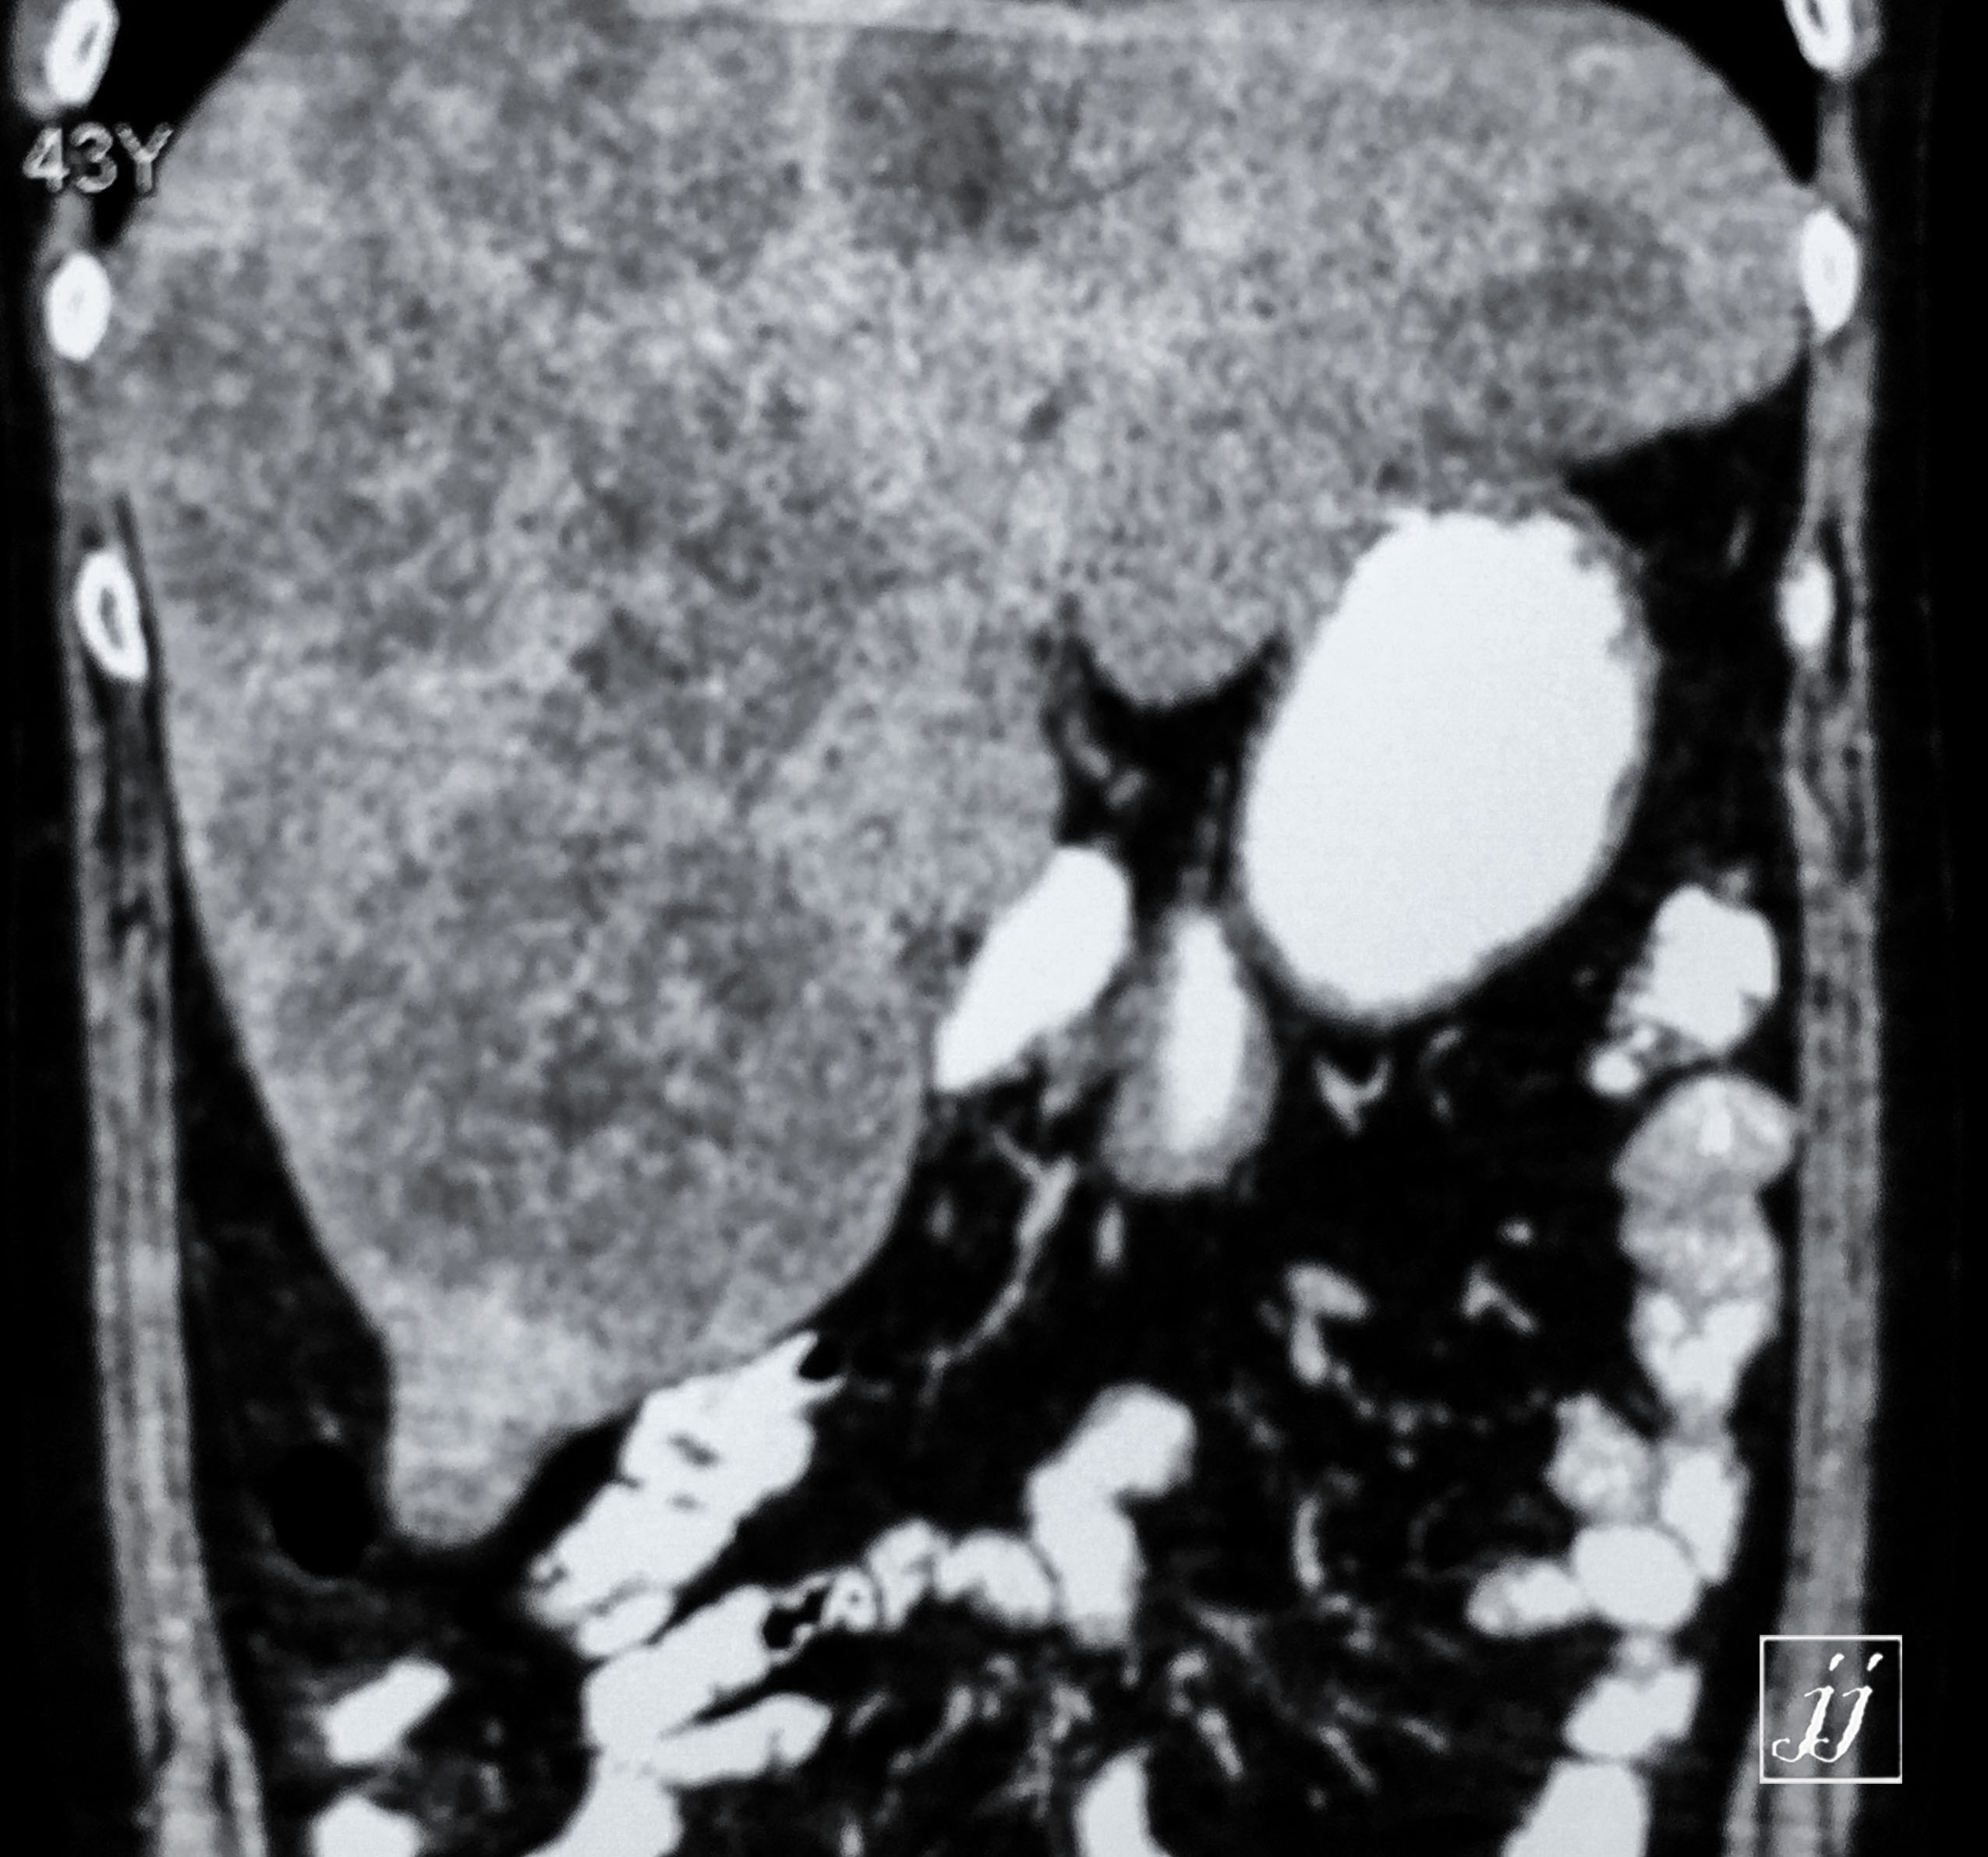

Abdomen- liver tumors and pancreas calcification vascular, gall bladder sedimentation, metastatic (11)Patient Data

Abdomen- liver tumors and pancreas calcification vascular, gall bladder sedimentation, metastatic (11)Patient Data